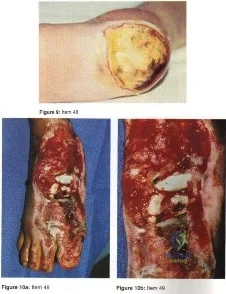

- a total contact cast.

- partial calcanectomy

- Syme’s amputation

- transtibial amputation.

- nonweightbearing and IV antibiotics.